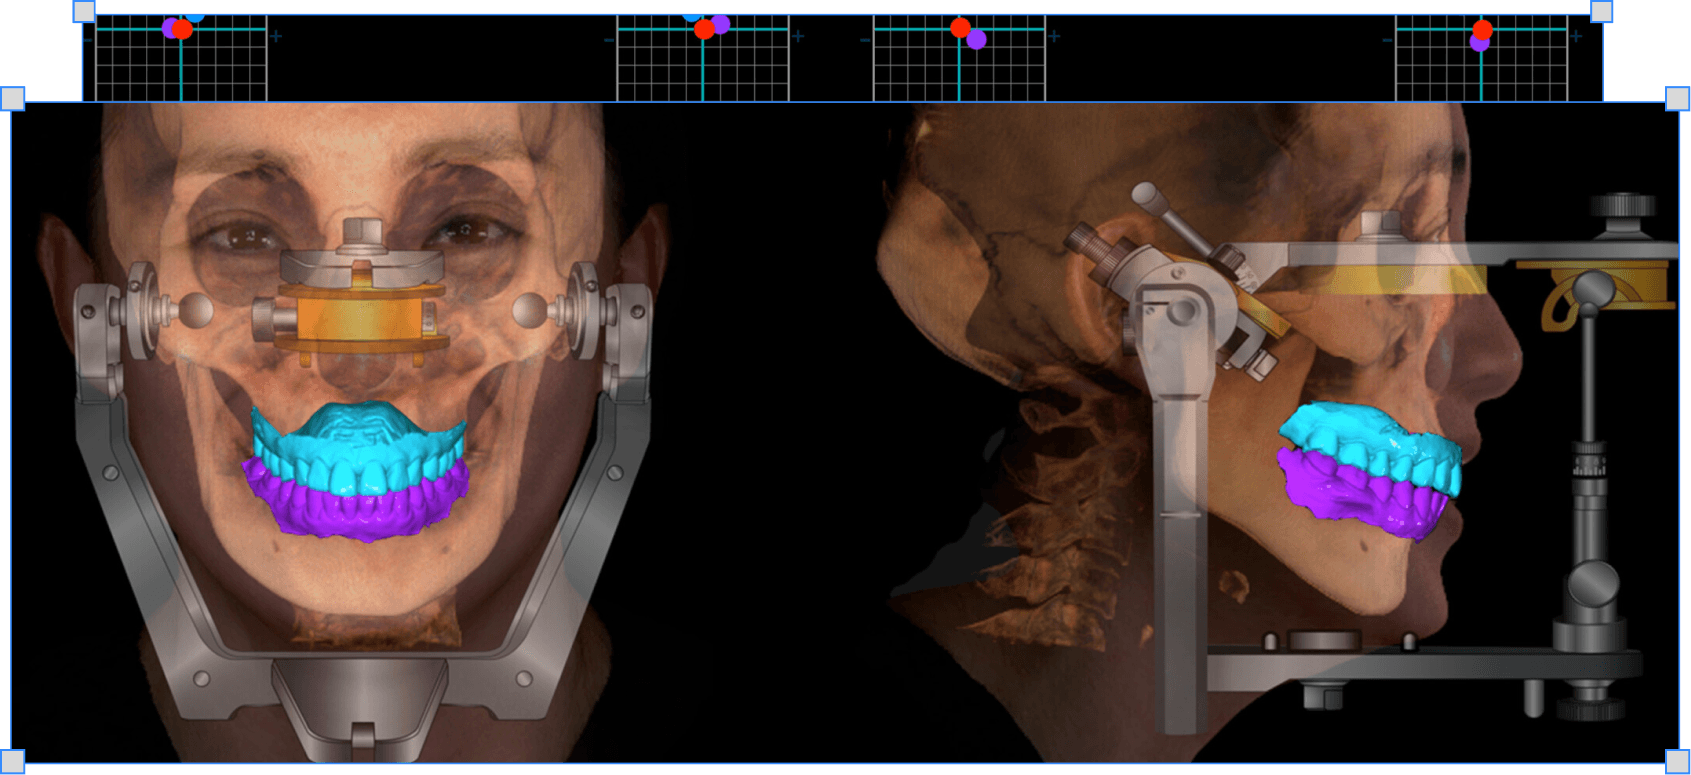

Ознаки бруксизму і дисфункції СНЩС, пальпація і міографія, воскова реєстрація щоб реставрація не дестабілізувала суглоб

Як знаходити центральне співвідношення

Чому звичне змикання і центральне співвідношення різні і як знайти повторювану позицію суглобу

→ Знаходиш повторювану позицію суглобової голівки для реєстрації

Як реєструвати центральне співвідношення

Яким воском і як робити реєстрацію щоб технік загіпсував моделі точно в центральному положенні

→ Технік гіпсує моделі в центральному співвідношенні без здогадок